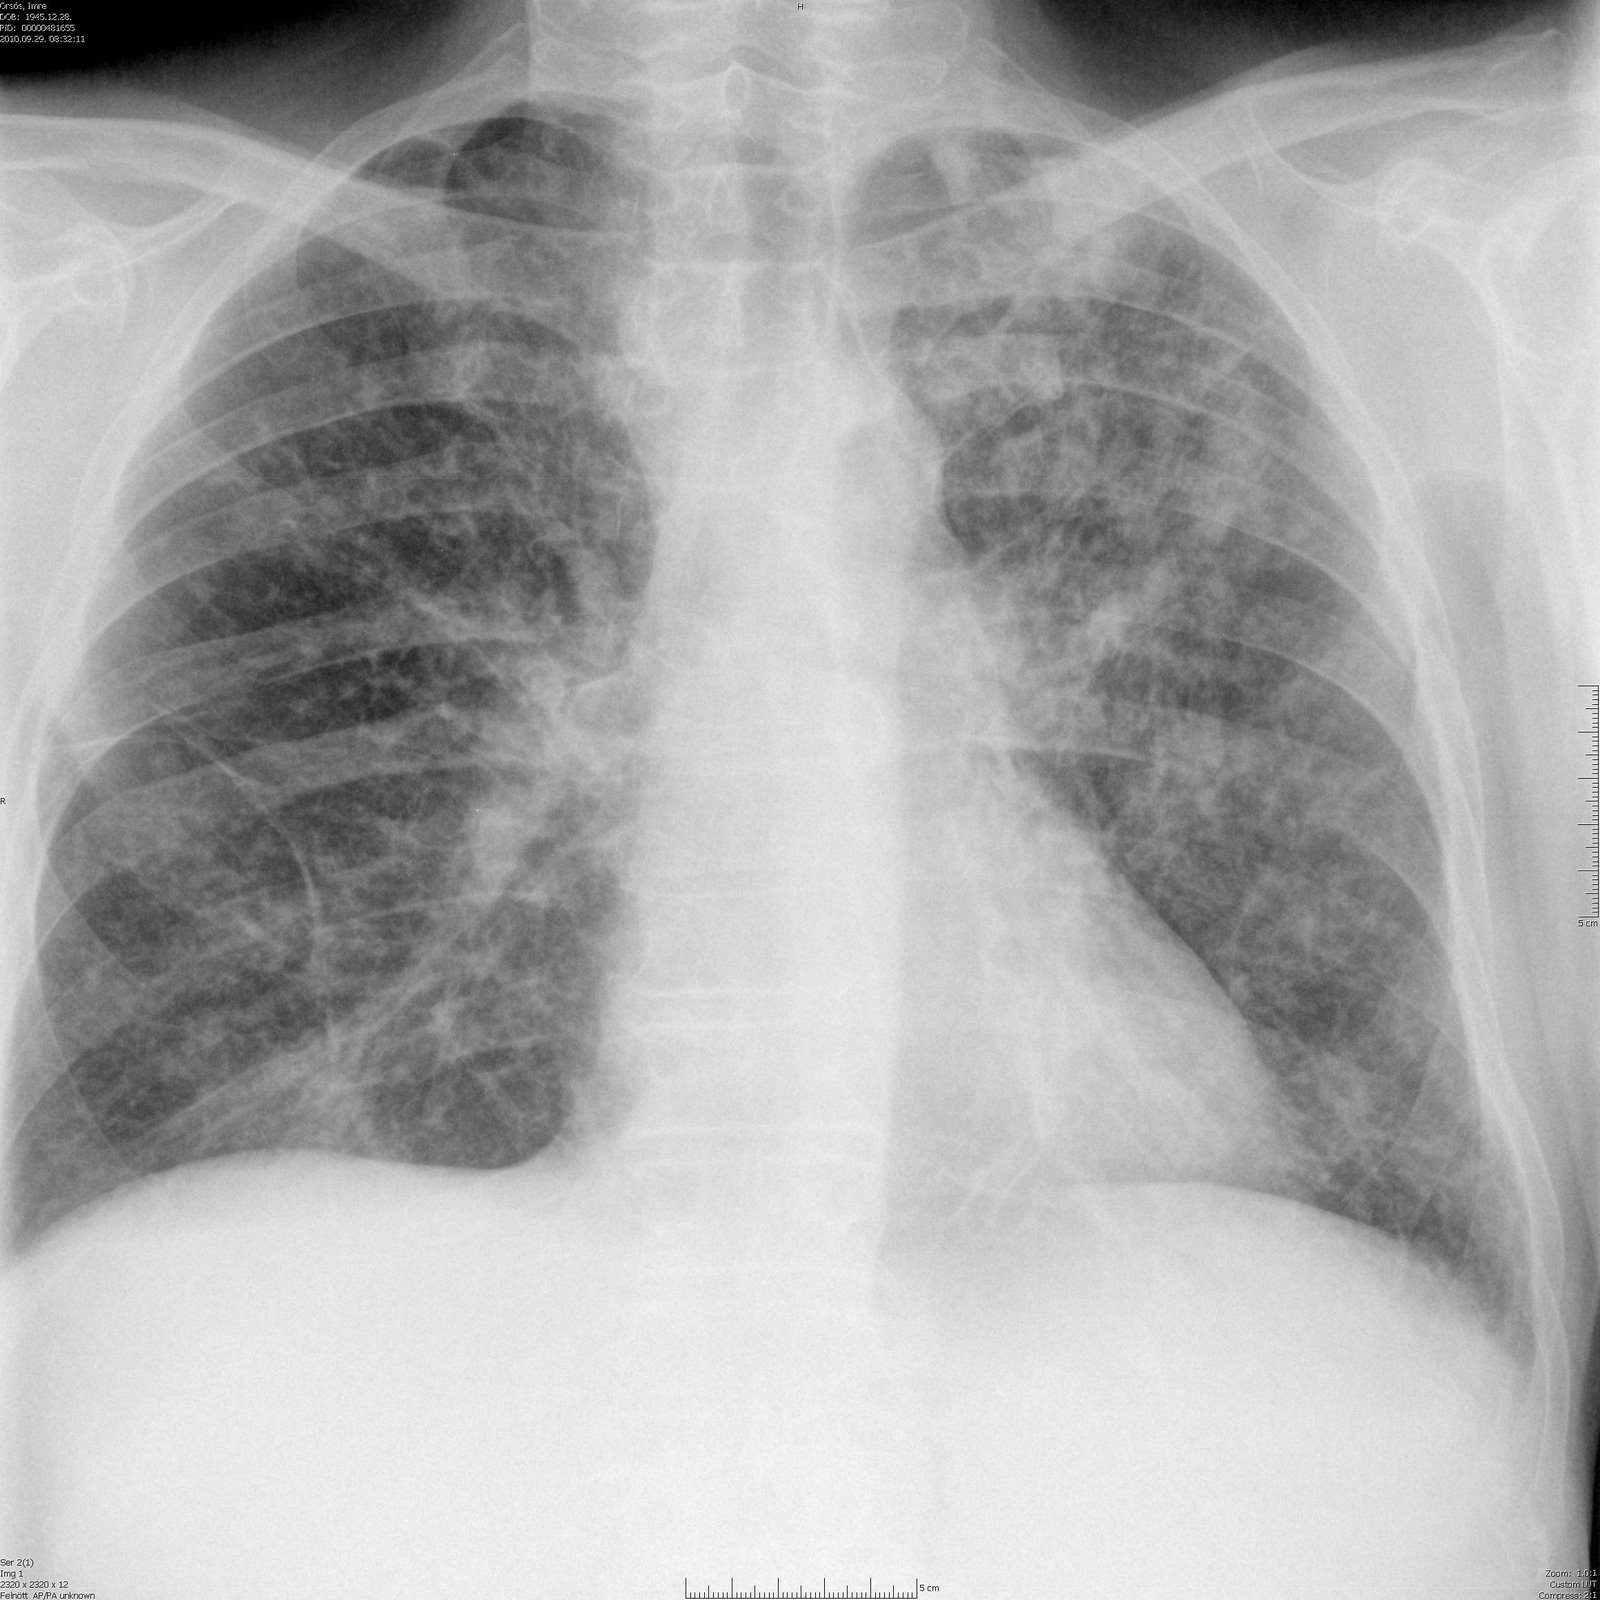

Korábbi, szintén tuberculoticus eredetű gyulladásos maradvány a bal tüdőcsúcsban, mely a hilust vongálja

Nyirokcsomók a mediastinumban, jobb oldali pleuralis folyadék